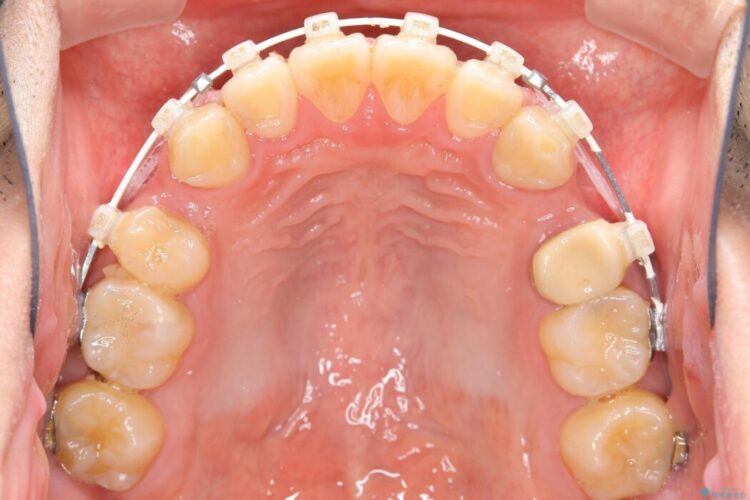

【30代男性】ワイヤー矯正で出っ歯とガタつきの改善

上の歯の出っ歯と下の歯のガタつきが気になるとご来院された患者様です。

出っ歯とガタつきの改善には抜歯が必要と診断し、上下左右第一小臼歯を抜歯することとしました。

抜歯でスペースができるため、歯の移動量が多いことから表側ワイヤー矯正装置で治療を行いました。